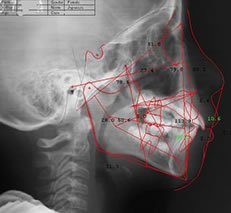

セファロ分析も実施

セファロは矯正治療専門のレントゲンです。通常のレントゲンとは異なり、頭部全体を正面と横から撮影できるため、歯をどのように動かし、また動いたのかを詳細に確認できます。矯正治療を行う際に、セファロによる分析は非常に大切です。